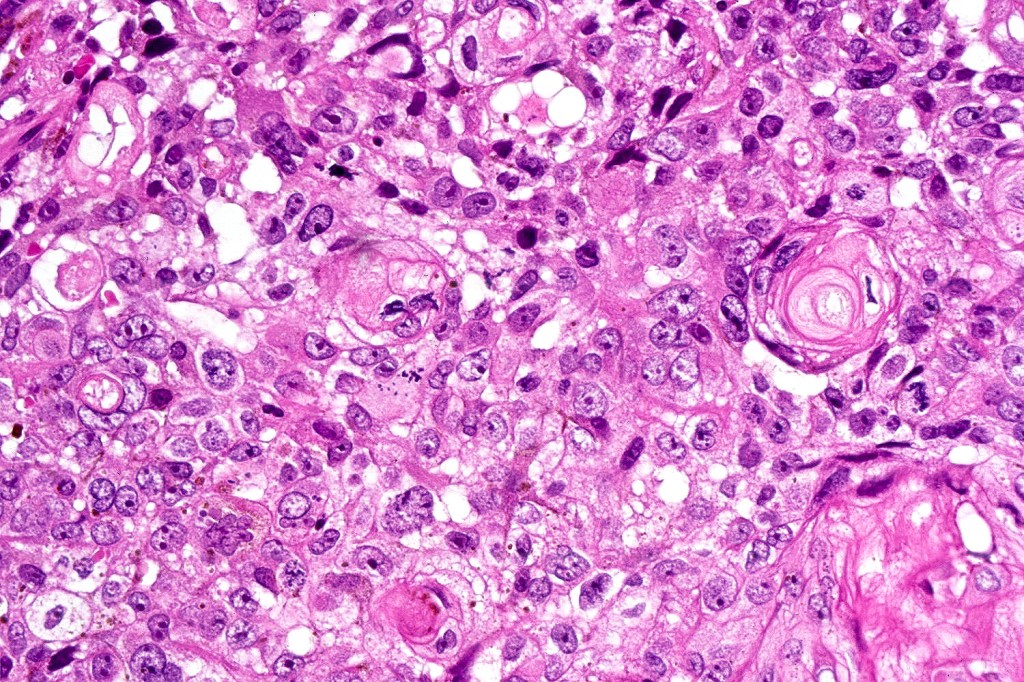

Histological features

•Well circumscribed nodular or multinodular growth pattern

•Admixture of basaloid matrical, supramatricial & eosinophilic shadow cells with dendritic melanocytes. The ghost cell change is distinctive affecting individual cells with preservation of their cytological detail rather than the en masse change typical of pilomatricoma

•Variable pleomorphism and mitotic activity affecting the matrical cells

•12 cases of the so-called malignant variant have been documented- characterized by ulceration, an infiltrative growth pattern and excessive mitotic activity- may recur but no evidence of metastatic disease or mortality has been reported